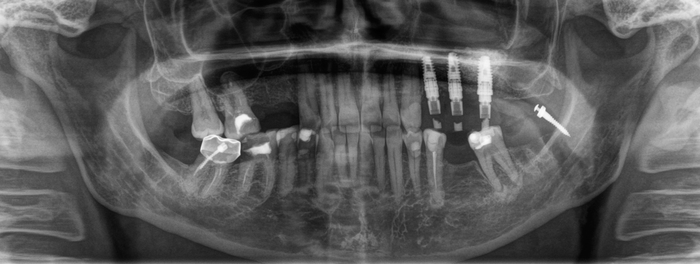

Для этого чаще всего используются ортодонтические минивинты. Для начала необходимо удалить зуб мудрости, потому как он будет только мешать (про зубы мудрости у меня есть целый ряд статей). Далее установить минивинт:

Вот эта белая палка справа – это и есть винт. Специфика этих винтов в том, что они не срастаются с костной тканью, а тупо вкручиваются в кость и держатся за счёт своей резьбы. Это позволяет без проблем и анестезии (!) выкрутить этот винт после окончания передвижения зуба.

Так вот: ортодонт дал тягу к винту при помощи специальных резинок. Далее пациентке необходимо будет посещать ортодонта 1-2 раза в месяц для замены тяг. Обычно такое передвижение занимает в среднем три месяца.

Вжух, три месяца прошло. Была проведена компьютерная томография для планирования имплантации. В связи с длительным отсутствием зуба костная ткань начинает постепенно убывать, что приводит к необходимости в костной пластике.

Пациентке была проведена костная пластика – пересадка костного блока (как это делается, читай тут) и установка имплантата (а об этом тут):

Этот снимок был сделан после операции. Если приглядеться, то можно увидеть область, откуда был взят костный блок, и его очертания в месте его фиксации винтиками:

Так как зуб встал на своё место, резиновые тяги были заменены на металлические лигатуры для того, чтобы просто зафиксировать положение зуба. Это вот те белые полоски, тянущиеся от зуба к винту.